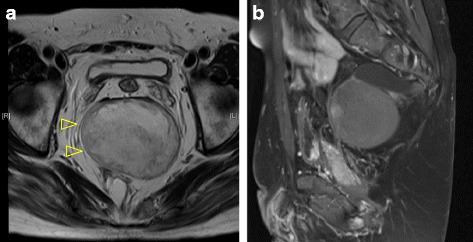

A 44-year-old man was diagnosed with Currarino triad, with a huge presacral teratoma and meningocele. One-stage surgery via posterior approach was successful.

一名44岁男性被诊断为库拉里诺三联征,伴有巨大的骶前畸胎瘤和脑脊膜膨出。通过后路进行一期手术获得成功。